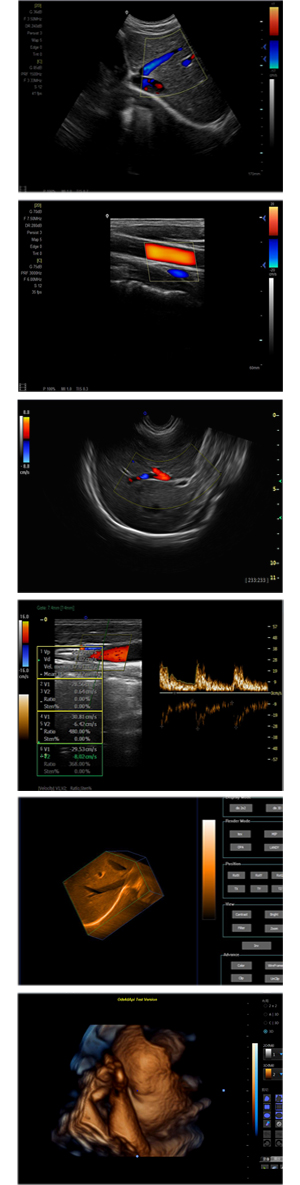

XF-7700型,秉承先鋒彩超技術(shù)之精華,擁有高雅大氣的獨(dú)特外型,為最新一代應(yīng)用型數(shù)字彩色多普勒診斷系統(tǒng),魅力與實(shí)力相融合。可廣泛適用于腹部、婦產(chǎn)科、心臟、小器官、乳腺、肌骨及外周血管等諸多方面的診查,讓您在臨床超聲診斷應(yīng)用領(lǐng)域得心應(yīng)手,綻放異彩!

● 3D/ 4D成像技術(shù)/選配

● 應(yīng)用于腹部、腎臟、泌尿系統(tǒng)、產(chǎn)科、婦科、盆腔、大動(dòng)脈、肌肉組織、小器官、乳腺、心臟等

● 能量多普勒成像(PDI)

● 彩色血流量圖(CDE)

● 脈沖頻譜多普勒成像(PW)